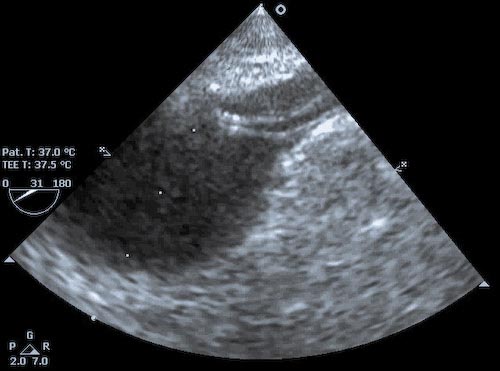

The figure to the left shows an IABP positioned slightly too high with the tip of the actual balloon just at the distal margin of the origin of the left SCA (visible from ~ 1-2 'o-clock). The IABP needs to be withdrawn in its femoral sheath by about 2-3 cm. In the image to the right, the tip of the IABP actually lies within the SCA, thus must be withdrawn a significant distance. Remember too that in the OR the patient may be positioned with legs flexed for vein harvest. Thus the IABP may well be pulled distally when the legs are returned to neutral. It is wise to recheck the position of the IABP with TEE prior to transport to the ICU.  Malpositioning of the IABP is NOT reliably detectable on the arterial waveform tracing - though low placement may show equalization of the IABP-assisted peak diastolic with the native-beat peak systolic pressure (which has other causes, eg: late inflation, balloon leaking, IABP too small for patient, or inflation volume set too low). Even when placed using echo guidance, it is imperative that IABP position be confirmed with CXR.